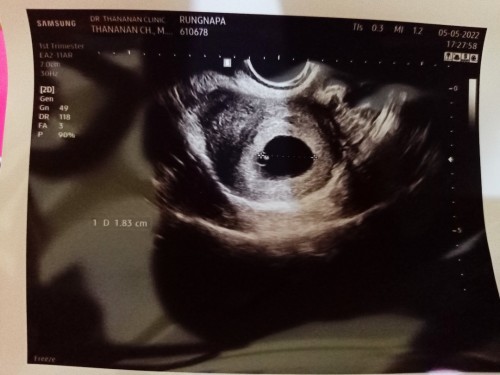

ขออนุญาตสอบถามค่ะ ประจำเดือนหนูขาดประมาณ 10 วัน ตรวจขึ้น 2 ขีด (ประจำเดือนมาล่าสุด 25 มีนาค่ะ) วันนี้ 5-5-2022 ไปอัลตราซาวด์คุณหมอแจ้งว่า พบถุงตั้งครรภ์ และถุงอาหารเลี้ยงตัวอ่อน แต่ยังไม่พบตัวอ่อน ตอนนี้กังวลมากเลยค่ะ ว่าจะมีโอกาสตั้งครรภ์หรือพบตัวอ่อนจริงหรือเปล่าคะ

เราซาวน์ครั้งแรกตอน 4w เจอแต่ถุงตั้งครรภ์ 0.5 cm ค่ะ หมอนัดอีกครั้งตอน 6w เจอตัวอ่อนกับหัวใจเค้าเต้นแล้วค่ะ ตัวอ่อน 0.77 cm ถุงตั้งครรภ์ 2.3 cm สู้ๆ นะคะ ทำใจให้สบายค่ะคุณแม่ เดี๋ยวก็เจอ

ตัวอ่อนพร้อมหัวใจมาประมาณ 7 วีคค่ะ แต่มีถุงตั้งครรภ์ และถุงอาหารก็อุ่นใจได้แล้วค่า แม่พักผ่อนเยอะๆนะคะ เดี๋ยวน้องก็มาค่ะ